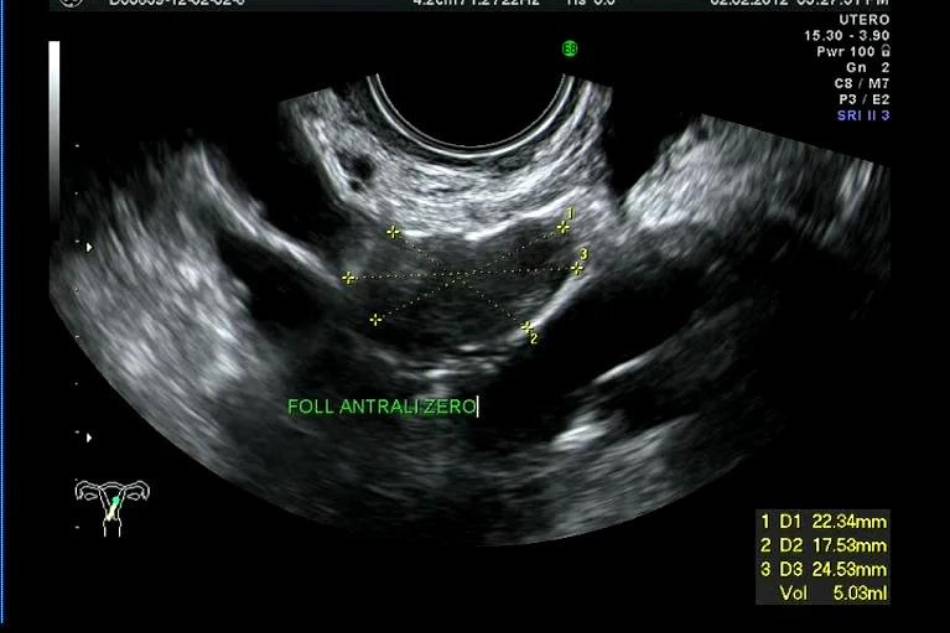

L’ecografia per il monitoraggio ovarico è una metodica ecografica per lo studio dell’ovulazione che permette una valutazione accurata della crescita follicolare sia in presenza di ciclo spontaneo sia nel caso di ciclo indotto farmacologicamente. Questa procedura prevede il monitoraggio ecografico dell’ovulazione effettuato attraverso una serie di ecografie trans-vaginali programmate secondo una certa periodicità per seguire lo sviluppo del follicolo o la stimolazione farmacologica delle ovaie.

L’esame ecografico è serve a valutare nello specifico le dimensioni dei follicoli ovarici, la loro crescita nel tempo e a descrivere l’aspetto e lo spessore dell’endometrio (lo strato più interno della parete dell’utero).

Da un punto di vista terapeutico, questa metodica può aumentare le probabilità di un concepimento perché permette di informare la coppia sul momento migliore in cui avere rapporti mirati alla procreazione, ovvero in corrispondenza dell’ovulazione. Mentre da un punto di vista diagnostico consente di verificare se l’ovulazione avviene o meno e, nei casi di fecondazione assistita, individuare il momento migliore in cui eseguire il prelievo di ovuli.